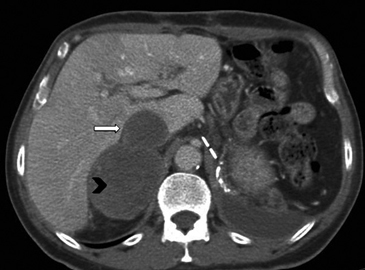

Figura 23. Carcinoma suprarrenal derecho. Corte axial de resonancia magnética ponderado en T2 con saturación grasa (a) en que se demuestra una masa suprarrenal derecha con áreas hiperintensas en su espesor probablemente determinadas por necrosis (flecha) y corte coronal en secuencia TRUFISP (b) en que se observa un trombo tumoral que expande el lumen de la vena cava inferior (cabeza de flecha).Puede también presentar invasión directa de otras estructuras vecinas, como riñón, páncreas, bazo y diafragma.